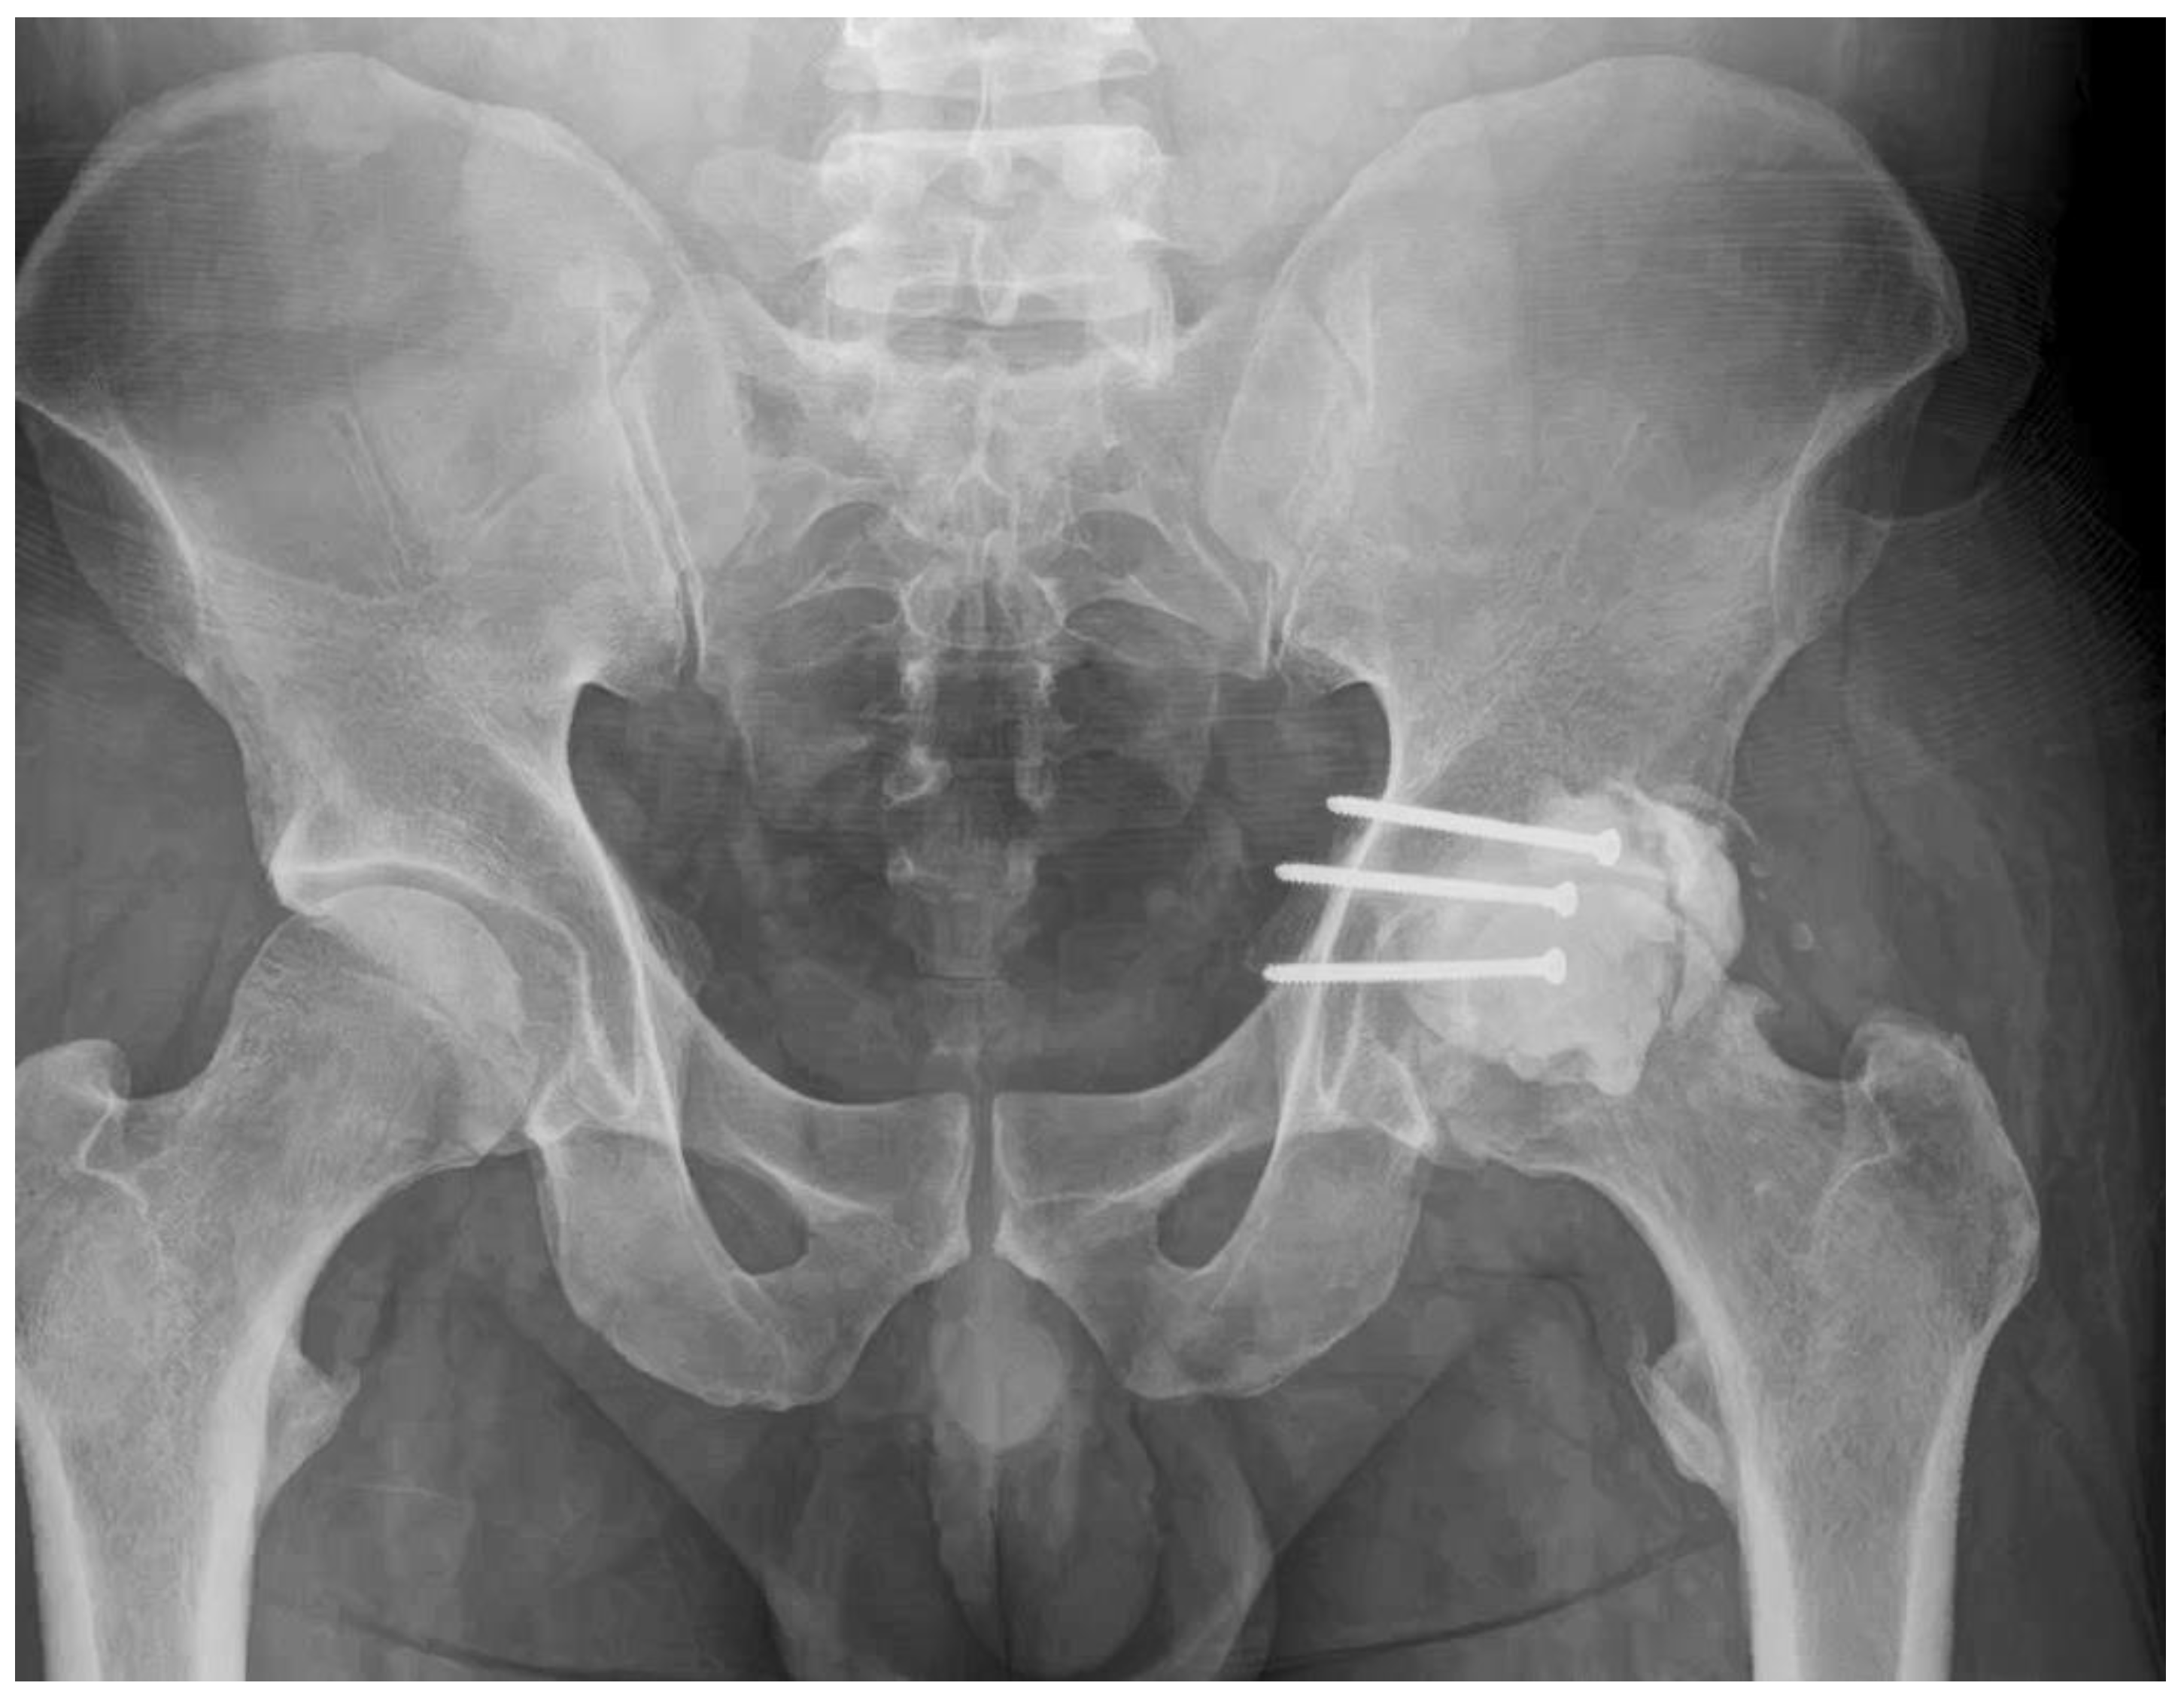

- 21 Months: AP pelvic radiographs showed excellent maintenance of joint space and a stable construct without loosening (Figure 9). The patient’s functional outcome was excellent, reporting no pain during daily activities, with only mild discomfort during deep squatting. The mHHS was 85/100.

- No radiographic evidence of cement loosening, screw migration, or secondary osteoarthritic change was observed at any follow-up interval.